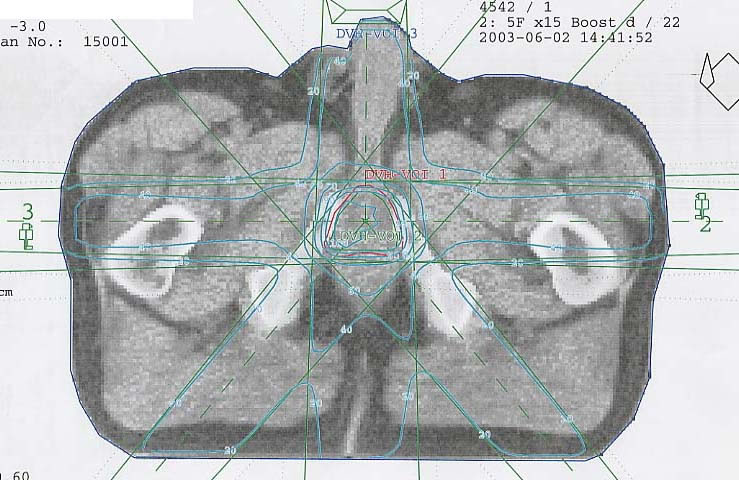

Prostatakarzinom: Bestrahlungsplan

Bestrahlungspläne